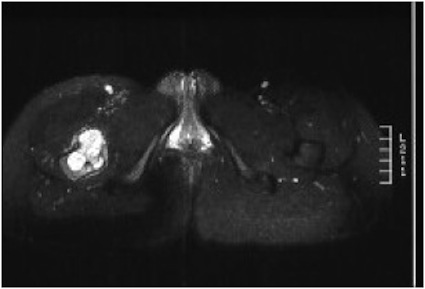

MRI

Low signal intensity of T1 / high signal intensity on T2

- intramedullary extent

Significant soft tissue mass with significant edema

Ewing's distal femur

Ewings iliac crest